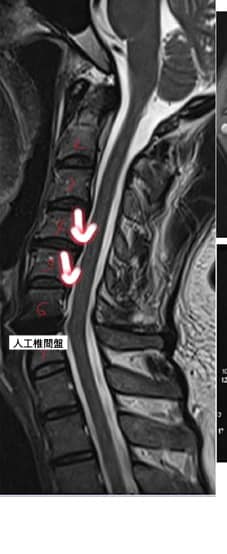

Cervical Spine Treatment Cases 頸椎治療案例 #疼痛三年頸椎病患者親手寫下治療紀錄 #交感神經型頸椎病 #症狀錯綜複雜 2020.10.02 #困擾四年多胸悶手麻頭暈醫案 #一切原因居然是頸椎出問題 #交感神經型頸椎病症狀錯綜... 2020.09.11 #交感神經型頸椎病引起的耳鳴 #耳鳴將近八個月終於得到重大改善 #曾經耳鳴到無法睡覺... 2020.08.22 #感謝板橋蘇先生熱情見證 #神經根型頸椎病卡壓 #曾痛痛到左手無法騎單車撥桿 #麻脹刺... 2020.08.04 #後縱韌帶鈣化引起椎管狹窄 #痛到完全無法睡覺長達半年以上 #原本已經準備開刀最後逆... 2020.07.16 #牽一頸而動全身的特殊醫案 #兩分鐘瞭解交感神經型頸椎病 #絕望的黑暗人生看到一絲希... 2020.07.03 #長達七年的頸椎疼痛是怎麼回事 #神經根型頸椎病 #低頭族跟家庭主婦辛苦了 #逆轉勝醫... 2020.07.01 #頸椎整合中醫微創療法 #感謝新竹黃大哥熱情見證 #逆轉勝成真醫案 2020.06.25 #頸椎病手術後也要要好好保健 #毛巾操很重要再度上場 #感謝某大醫學中心主任見證 2020.06.24 #這些症狀很可能都是頸椎出問題 #患者看七種不同科別醫師找不出原因 #交感神經型頸椎... 2020.06.09 #消失的頸椎曲線能夠回來嗎? #核磁共振前後對比椎管容積打開 #脊椎整合中醫微創療法❤... 2020.06.05 #感謝新竹薛大哥熱情見證 #頸椎整合中醫微創療法 治療:4/21~5/30(八次) 效果顯著... 2020.05.30 從宜蘭來的游小姐患者熱情見證 頸椎整合中醫微創療法 逆。轉。成。真。 2020.05.29 #脊髓型頸椎病案例 2020.05.26 #感謝新北市黃小姐熱情見證 #疼痛時間超過一年 #晨起麻痛到不行的日子長達半年以上 #... 2020.05.16 ← 上一頁 5 6 7 8 9 下一頁 →